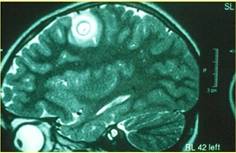

Bệnh ấu trùng sán lợn (Cysticercosis)

-Triệu chứng thần kính trung ương: động kinh là hay gặp nhất, nhức đầu, não úng thủy, ảnh hưởng tủy sống, 25% trường hợp xuất hiện các nốt dưới da có thể sờ thấy được;

-Chẩn đoán thông qua hình ảnh của chụp cộng hưởng từ (MRI)/ CAT scan; chẩn đoán huyết thanh dương tính chỉ trong 60%;

-Điều trị chủ yếu bằng Albendazole + Steroids